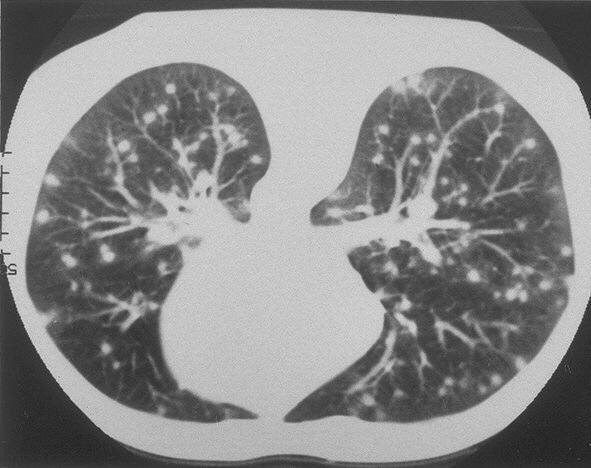

Example 2: restoration of images corrupted by blur and SPN or AWLN. In this example we evaluate the performance of the proposed TV-L1 model on three medical test images lungs (), Fig. 5 (a), ecography (), Fig. 6 (a), and aneurism (), Fig. 7 (a), synthetically corrupted by Gaussian blur of parameters band=5 and sigma=1 and by two types of impulsive noise, namely SPN and AWLN.

The images are provided in the repository at https://medpix.nlm.nih.gov.

![]() |

| (a) original | (b) TV-L1 (ISNR = 11.04) | (c) zoom of (b) |

| (d) corrupted | (e) TVp-L1 (ISNR = 12.48) | (f) zoom of (e) |

| (g) -map () | (h) TV-L1 (ISNR = 15.30) | (i) zoom of (h) |

| (l) -map () | (m) TV-L1 (ISNR = 16.56) | (n) zoom of (m) |

First, for what concerns corruptions by SPN, in Figs. 5, 6, 7 we report for the three considered test images the original and corrupted image together with the estimated -maps in the first column (with the size of the neighborhoods used for the -maps estimation reported in the captions), the restoration results, obtained by the four compared methods, in the second column (with the achieved ISNR values in the captions) and a zoomed detail of the restored images - green- bordered in Figs. 5 (a), 6 (a), 7 (a) - in the last column.

The reported ISNR values as well as the visual inspection of the restored images and of the zoomed details strongly indicate how the proposed space-variant regularizer allows for higher quality restorations. In particular, it is worth remarking how, with respect to the space-variant TV model, the additional degrees of freedom represented by the scale parameters used in our proposal, yield a sufficient additional flexibility for avoiding unwanted spurious effects - see, e.g., spikes in Figs. 5 (i), 6 (i), 7 (i).